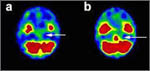

Investigatii efectuate ziua urmatoare au aratat o regiune hipoperfuzata la nivelul trunchiului cerebral, mai extinsa decat hemoragia pontina (figura 3a). Pentru tratamentul celor gasite a fost crescuta volemia, continuandu-se insa administrarea medicatiei hipertensive.

Investigatii ulterioare au evidentiat hipoperfuzia emisferei drepte, partea inferioara, a cerebelului, hemoragia pontina incepand sa se remita la aceasta data.